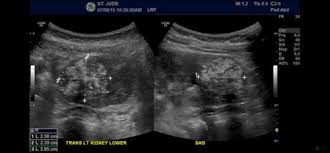

An atypical teratoid rhabdoid tumor (atrt) is a very rare, aggressive tumor of the central nervous system, occurring mostly in the cerebellum, the part of the brain that controls movement and balance, or the brain stem, the part of the brain that controls basic body functions. What are the signs and symptoms of a pediatric atypical teratoid rhabdoid tumor (atrt)? Symptoms of atrt may include the following: To get an accurate diagnosis, a piece of tumor tissue will be removed during surgery, if possible. Mri of an atypical teratoid rhabdoid tumor (atrt) in the brain.